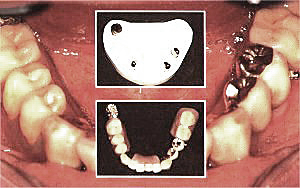

Die Geschiebe - Prothese besteht aus Kronen mit Geschieben, d.h. einer Kombination aus festsitzendem und herausnehmbarem Zahnersatz. Zum Beispiel werden Frontzähne dabei durch Kronen oder Brücken festsitzend ersetzt. Der herausnehmbare Teil des Zahnersatzes ist über unsichtbare feinmechanische Hilfsteile an den Kronen befestigt. Passform und Handhabung eines Geschiebes sind perfekt. Auch ästhetische Wünsche können weitestgehend berücksichtigt werden.